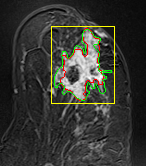

In MR images, tumor regions are normally brighter and have more uniform intensity than the neighbouring healthy tissue. Based on this fact, we determined the internal and external markers by sorting out the pixel values in ROIs in descending order and chose pixels with maximum intensity values as markers. After selecting the markers the normal watershed transformation is applied on the ROIs image which is shown in Fig 1 Finally, a binary mask is generated based on watershed output regions. However, we identified the optimal number of markers based on segmentation accuracy evaluated using Dice and Jaccard.

We tested the algorithm by varying the number of markers between and . Fig 2 describes the segmentation results obtained using different numbers of markers. This plot indicates that markers were found to be optimal using this segmentation approach, yielding satisfactory results.

where refers to the ROIs segmented by our algorithm and is tumor area as determined by manual segmentation. Table 1 summarizes the segmentation accuracy achieved using the proposed method for all 106 cases. The average dice coefficient was found to be 0.780.17 and average Jaccard index was 0.670.21. Fig 3 demonstrate four sample segmentation outputs which are overlaid on manual segmentations provided by two radiologists. It can be seen, that the proposed method could accurately segment the lesions with some marginal errors for medium to large tumors. However, for cases comprising disjoint lesions, the method failed to segment all small lesions and in some cases incorrectly labeled healthy tissue as lesions. This is because in some cases there is a high degree of overlap in the intensity distributions of healthy breast tissue and lesions, and the ROI drawn by the radiologist is very large in the case of disjoint lesions, in order to cover the entire area over which multiple lesions are distributed.